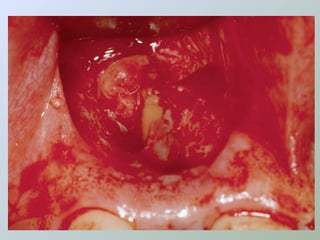

Caso 1

Caso 2

Paraendodôntica uepg